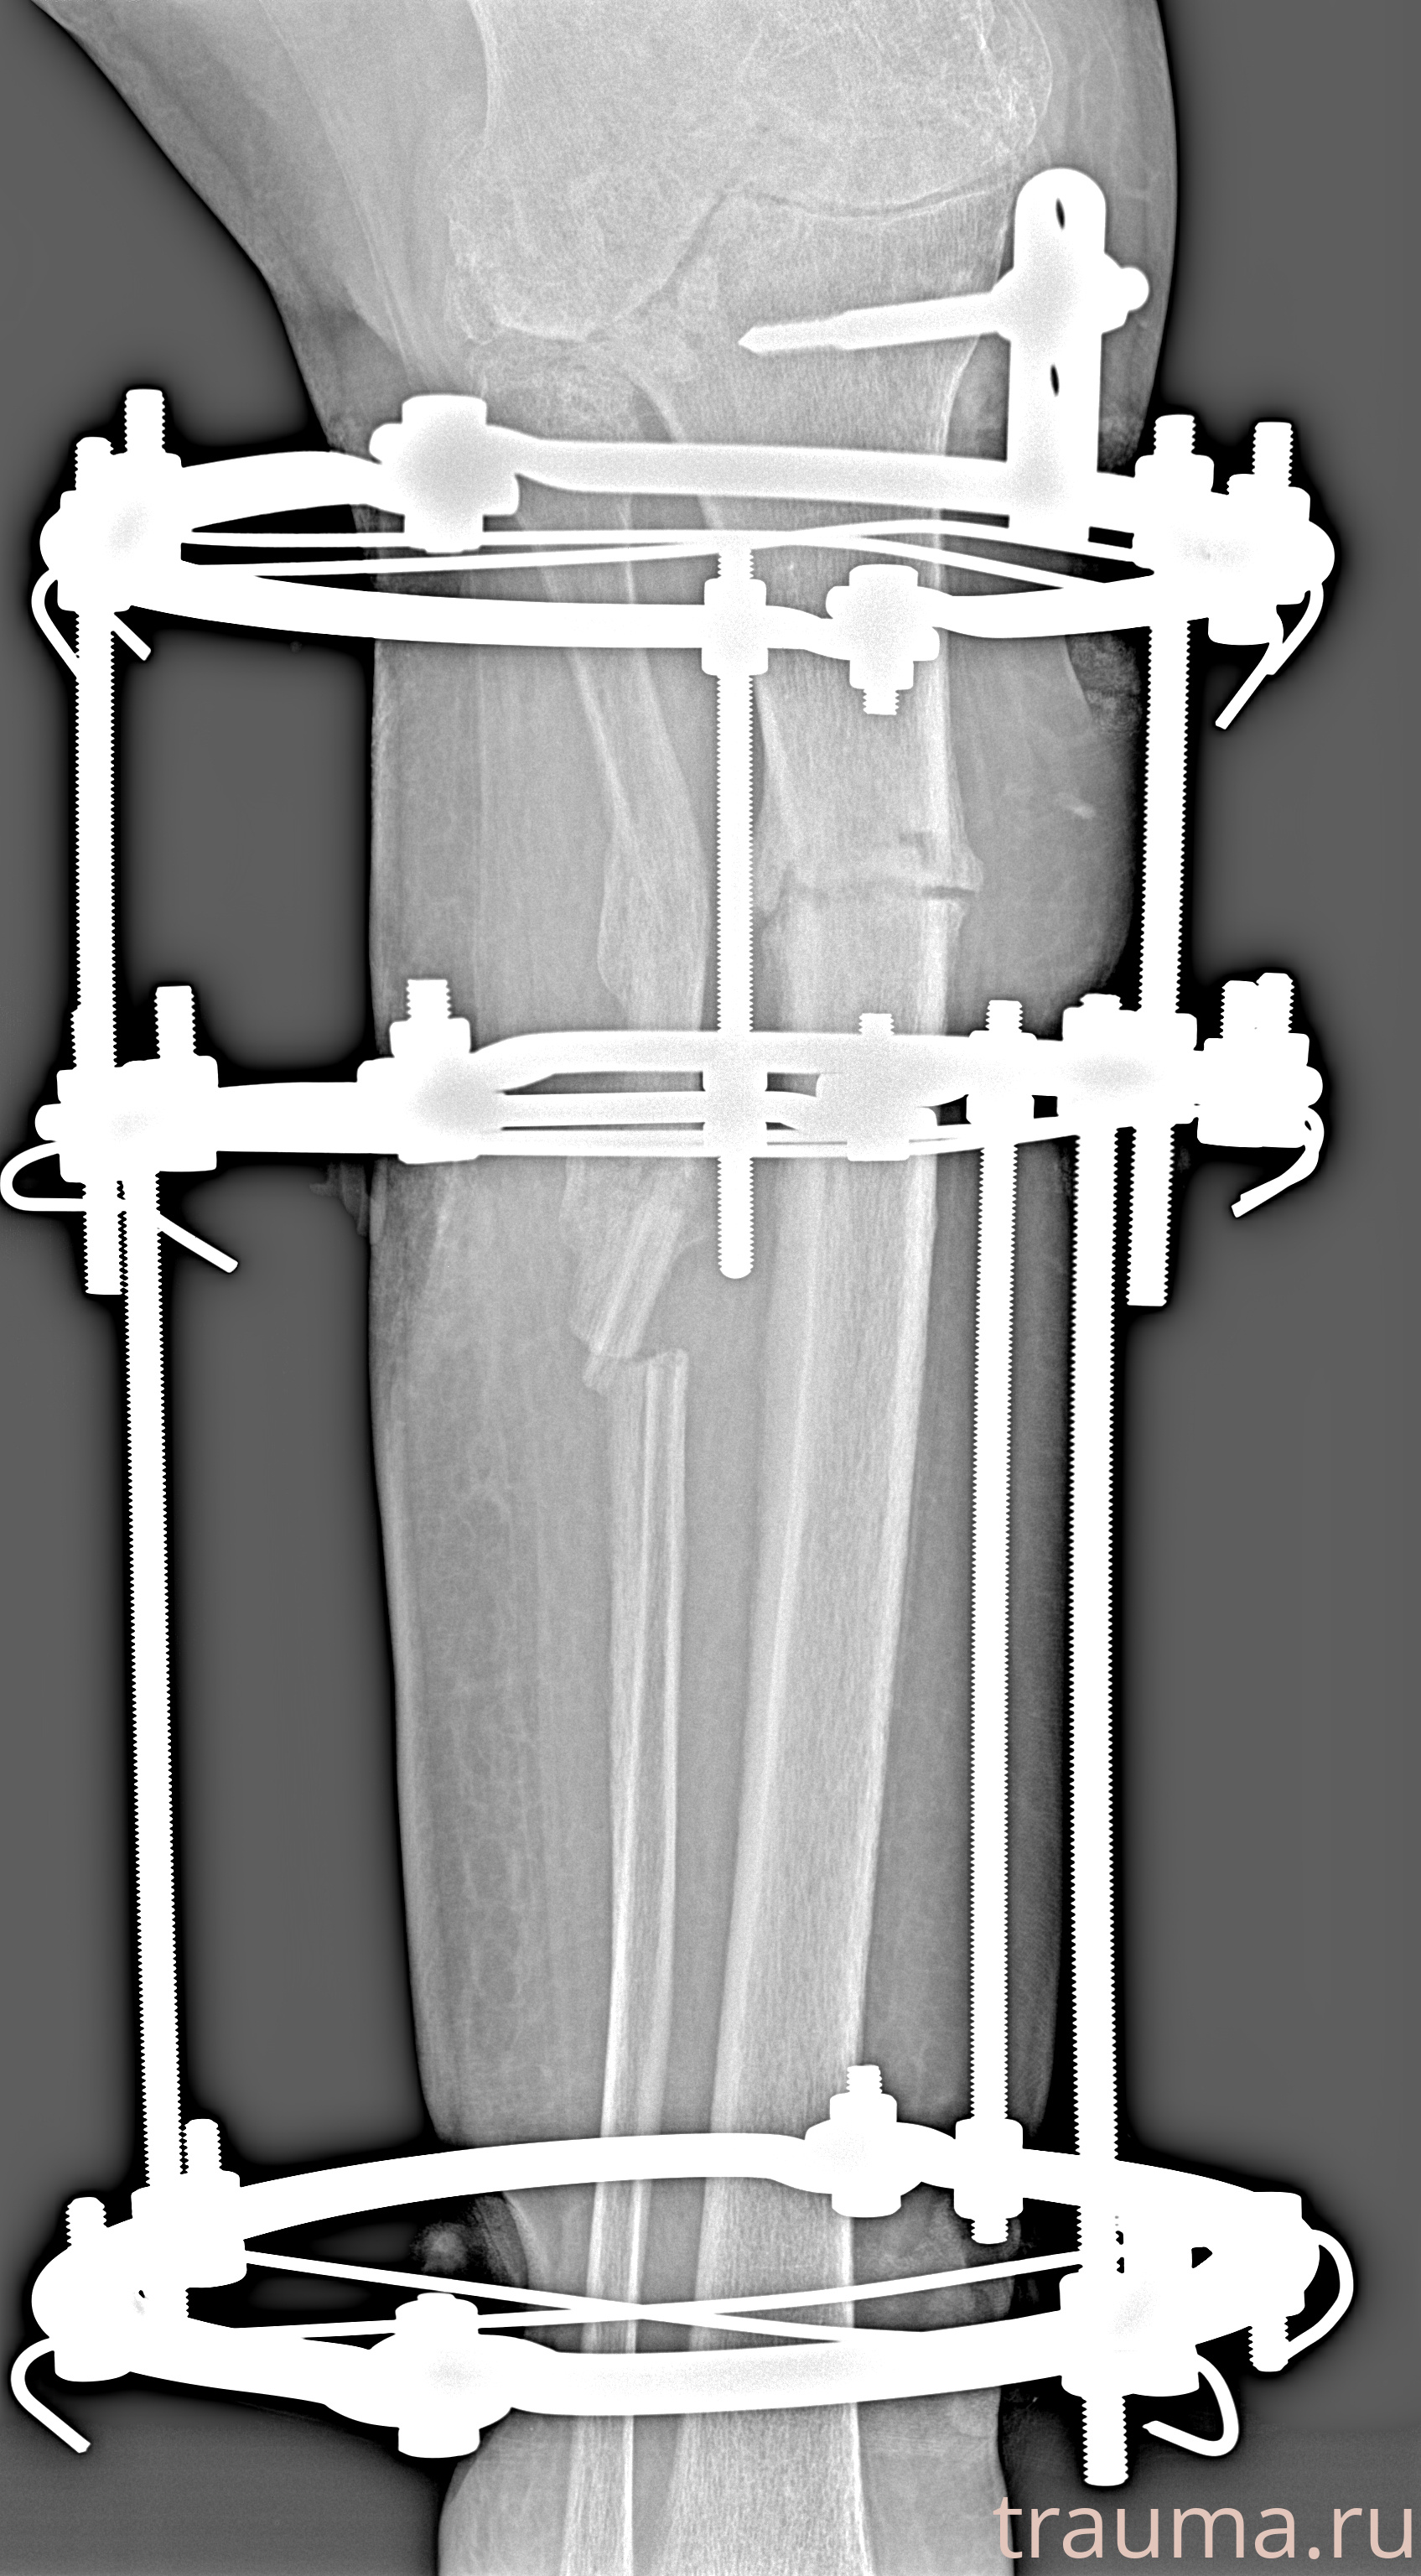

Рентгенограммы

Левая

Рентген на дому: по вашему адресу приезжает врач-рентгенолог, травматолог-ортопед с мобильным рентгеновским аппаратом, проводит диагностику травмы или заболевания, делает необходимые рентгенограммы, дает рекомендации по дальнейшему лечению. Получить качественные снимки в домашних условиях возможно благодаря уникальной методике, разработанной МосРентген Центром для института  Склифосовского